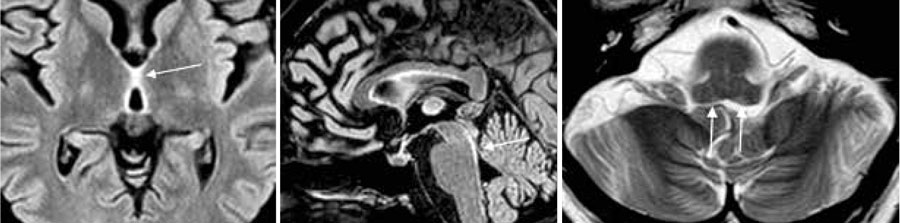

Fallbeskrivning Ett tidigt och specifikt kliniskt tecken vid Wernickes encefalopati